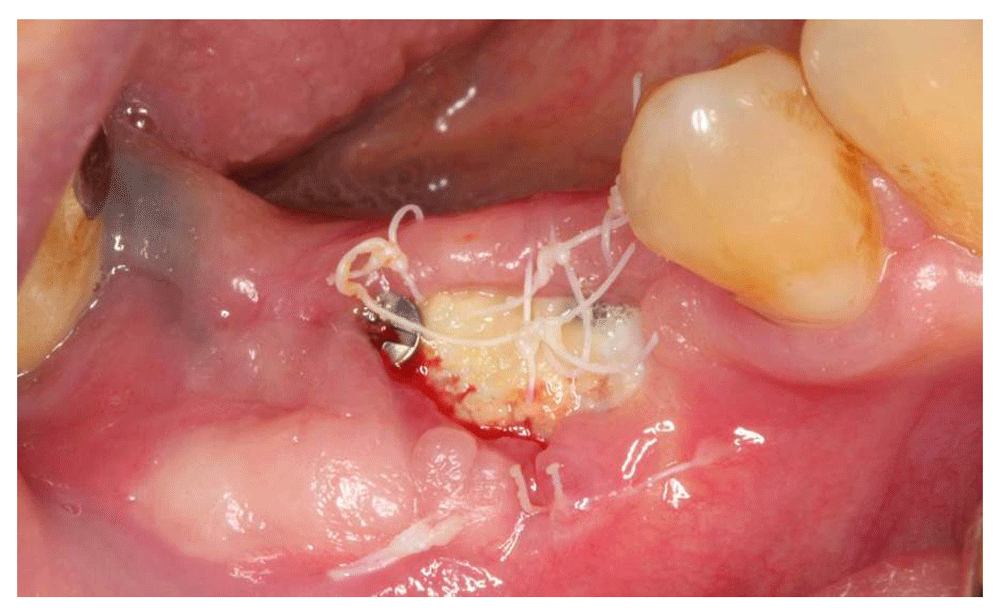

Bone Grafting 8, dPTFE Membrane Removal at 28 days YouTube Removing Dental Membrane Read our bone grafting & membrane placement instructions following your procedure. This depends entirely on the graft material , it is critical on most graft materials but there a newer materials where the graft is both. 4/5 (16) Many stitches will then hold the membrane and graft into place. A dental bone graft is a surgical procedure that involves. Removing Dental Membrane.

Bone Grafting 8 Site, Membrane Removal at 28 Days YouTube Removing Dental Membrane A dental bone graft is a surgical procedure that involves transplanting bone tissue into the jaw or oral cavity to promote bone growth and regeneration. The bone grafting material consists of granules of bone that will fill the entire tooth socket. Many stitches will then hold the membrane and graft into place. This depends entirely on the graft material ,. Removing Dental Membrane.